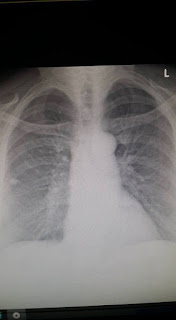

Healthy Lung xray

Side view, all the white is stria marks.....not a good thing in your lungs